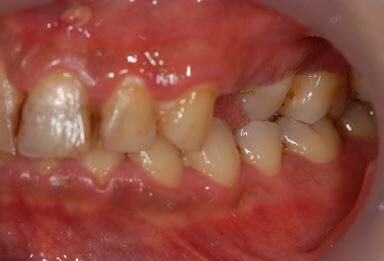

| 性別/年齢 | 男性 / 36歳 | ||||||||||||||||||||||||||||||||

| 主訴 | 歯が折れているので、インプラントにしたい。 | ||||||||||||||||||||||||||||||||

| 治療方針 | 抜歯と同時にインプラント埋入を行い、治療期間を短縮する。 | ||||||||||||||||||||||||||||||||

| 治療内容 | インプラント2本(抜歯即日インプラント治療)、ジルコニアフレームオールセラミッククラウン1本、オールセラミッククラウン2本(セラミック用土台2本)、メタルボンドセラミッククラウン1本 | ||||||||||||||||||||||||||||||||